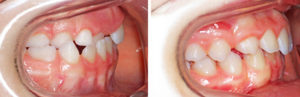

Ci-dessous les photos avant et après traitement, vues de profil (cliquez sur l’image pour l’agrandir) :

Voici l’exemple d’un patient enfant traité par le Dr Issembert au cabinet d’orthodontie à Paris.

On distingue :

- un articulé croisé antérieur sur une dent,

- un articulé croisé postérieur, à gauche sur la photo : l’incisive est rentrée vers l’intérieur

- ainsi qu’un articulé croisé postérieur, au fond à gauche sur la photo : les dents du haut sont à l’intérieur des dents du bas

Plusieurs cas d’articulés-croisés – antérieur et postérieurs – traités en orthodontie chez un enfant

Ce patient a d’abord eu un disjoncteur afin d’élargir l’arcade supérieure. Ensuite il a été traité en 10 mois à l’aide de bagues externes en céramique afin de réaliser l’alignement. Une deuxième phase de traitement à l’adolescence est en cours, afin de réduire le recouvrement.